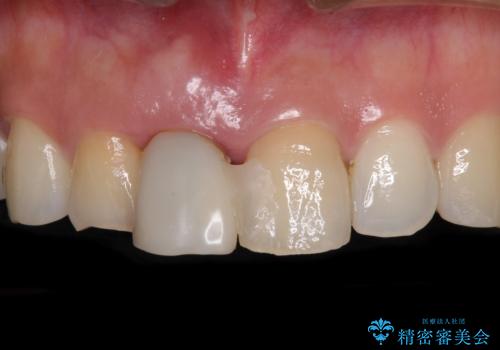

- 仮歯のまま前歯を放置しているとのことで来院された患者様です。

目視で確認できるほどしっかりとした破折が認められ、抜歯が必要と判断されました。

抜歯後は歯肉が痩せてしまうため、歯肉移植を行って歯肉の形態を改善した後、オールセラミックブリッジにて補綴することとしました。